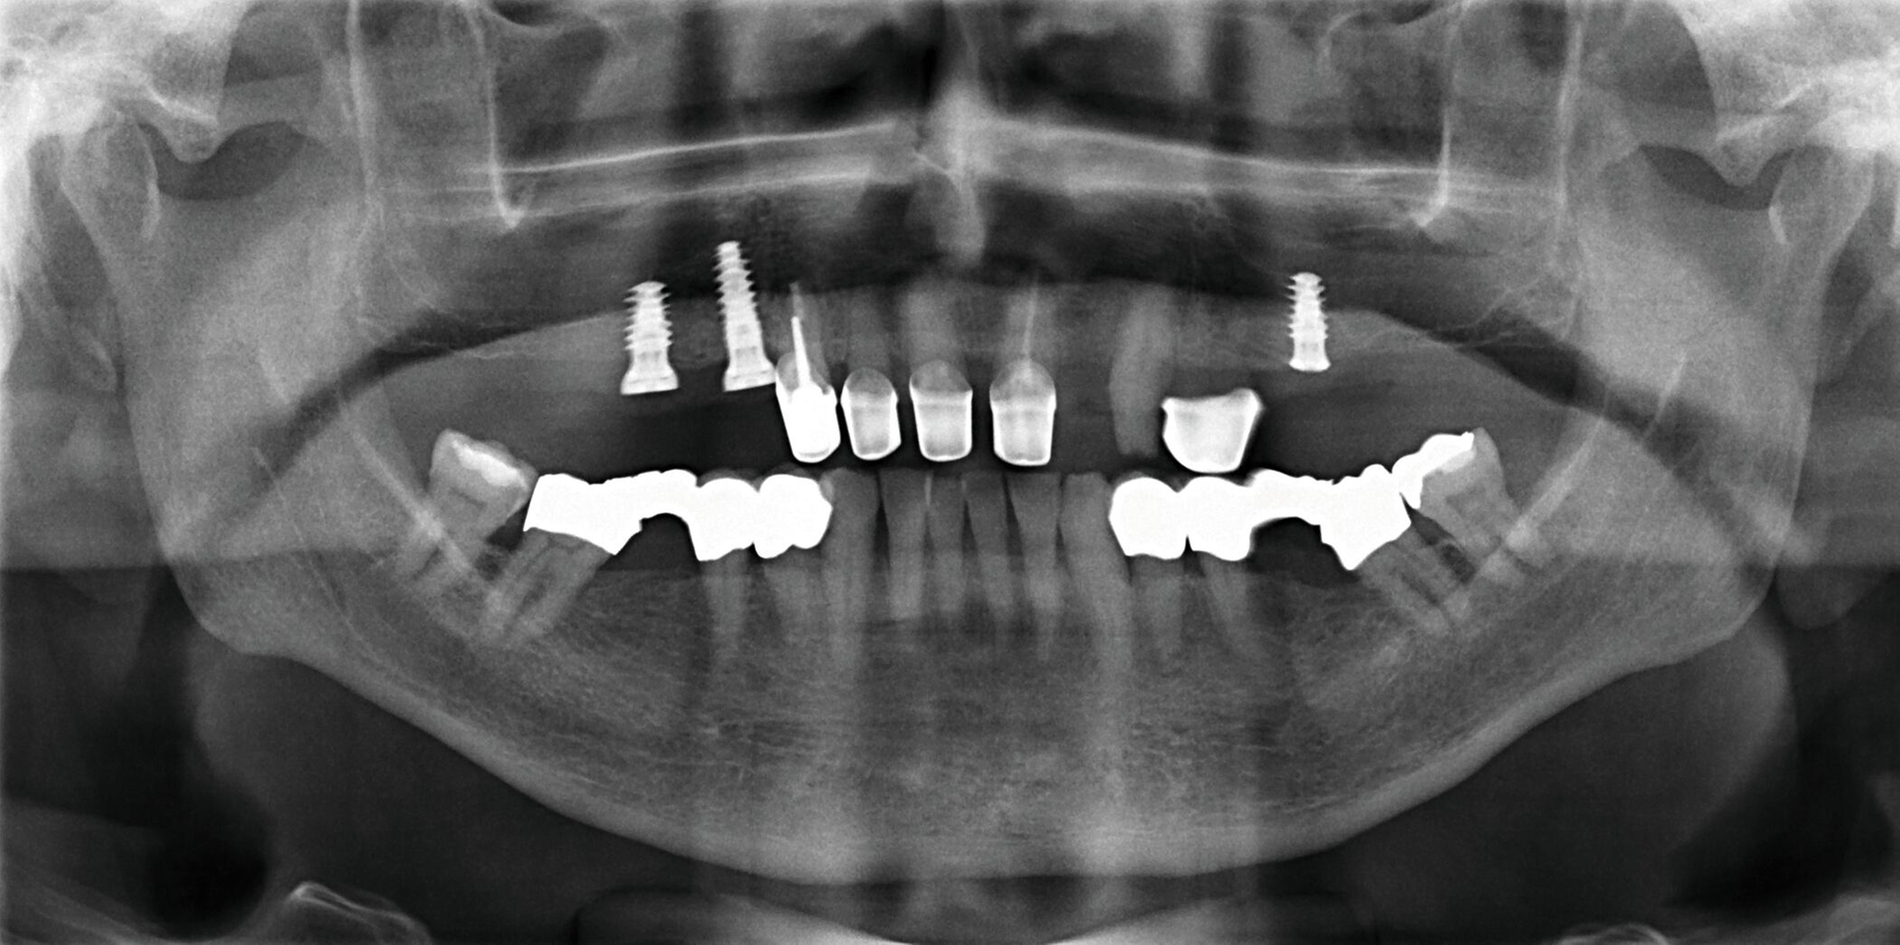

Der Patient stand unter der Dauermedikation von Metformin 500 mg, Ramipril 5 mg, Torasemid 10 mg, Metohexal 47,5 mg, Simvastatin 20 mg, Tamsulosin 0,4 mg und 3 mg Marcumar (INR 2,5–2,8) bei Zustand nach einer Bypass-Operation im Jahr 2019. Klinisch zeigten sich im Oberkiefer insuffiziente, verblockte und verblendete NEM-Kronen mit beidseitigen Gold-Extensionen distal, die über Geschiebe mit dem anterioren Anteil verschraubt waren (Abbildungen 1 und 2). Der Patient berichtete, dass die vorhandenen Kronen und Brücken 1984 eingesetzt worden seien.

Besonders auffällig war eine Dezementierung, die klinisch durch rechtsseitigen Druck und Zug mit einer Pinzette und daraufhin austretende Sulkusflüssigkeit in Regio 14 detektiert wurde. Da entsprechend des synoptischen Behandlungskonzepts [Naumann et al., 2010] bei prothetischer Neuversorgung eine gesamte Evaluation der Restpfeiler erfolgen muss, wurden zunächst die Kronen im Oberkiefer durch Schlitzen und Aufbiegen entfernt. Erst danach ließ sich deren Erhaltungswürdigkeit abschließend beurteilen.

So war der Zahn 14 tief kariös zerstört und nicht-erhaltungswürdig, was mit dem Bild der wahrscheinlich seit Längerem bestehenden Dezementierung korrelierte (Abbildung 3). Die Brücken im Unterkiefer wurden als suffizient befundet. Die Ruheschwebelage wurde mithilfe des Zielinsky-Zirkels auf 2 mm bestimmt. Parodontologisch zeigten sich stabile Verhältnisse. Ein Parodontaler Screening-Index (PSI) wurde erhoben (3-1-1-1-2-2). Der hier auffällige Zahn 14 wurde bereits zuvor beim klinischen Befund als nicht-erhaltungswürdig eingestuft und im Verlauf extrahiert.

Nach Durchführung einer dentalen Volumentomografie (DVT) wurden daher zahnärztliche Implantate in Regio 14, 15 und 25 im Sinne einer verkürzten Zahnreihe geplant und inseriert (Abbildung 7). Nach dreimonatiger subgingivaler, konventioneller Einheilzeit wurden die Implantate freigelegt. Zwei Wochen später begann man die vorhandenen Primärkronen zu entfernen. Die Stümpfe wurden nachpräpariert und es wurden erneut Fäden gelegt (Abbildung 8a und 8b).

Um den Sitz der Implantatkronen nach dem Einsetzen zu prüfen, wurden intraorale Tubusaufnahmen im Sinne eines Baseline-Röntgens angefertigt (Abbildung 9). In den Folgeterminen wurde dem Patienten noch eine Aufbissschiene für den Oberkiefer eingegliedert, um etwaigem nächtlichen Bruxismus vorzubeugen. Für die Nachsorge empfiehlt sich ein halbjährliches Kontrollintervall.